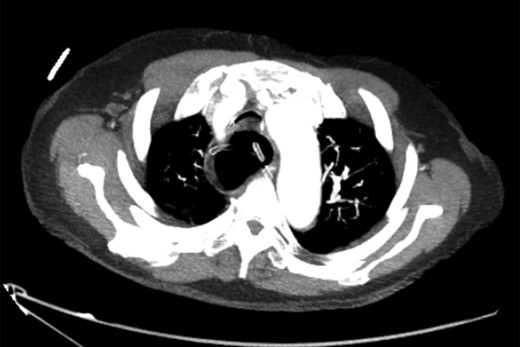

After decompression of the oesophagus, a computed tomography (CT) scan of the chest confirmed the diagnosis of megaoesophagus causing tracheal compression. The patient, now stabilized, was referred for oesophago-gastro-duodenoscopy (OGD) with a view to Botulinum toxin treatment for underlying achalasia (Figures 1–3).

Axial slice of CT chest after nasogastric decompression showing persistent megaoesophagus and airway narrowing.